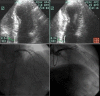

Background: Exercise echocardiography (EE) is an established method to diagnose coronary artery disease (CAD). Chronotropic incompetence (CI) during the EE may be a marker of myocardial ischemia. The purpose of this investigation was to evaluate the additive value of CI during EE in CAD diagnosis.

Methods: Between 2000 and 2006, 4042 patients (1900 men with a mean age of 56 +/- 11 years) were evaluated by EE. Based on the heart rate (HR) reached during the exercise test, the subjects were divided into two groups: G1 group - 490 patients who failed to achieve 85% of the maximal age-predicted HR, and G2 group - 3552 patients who were able to achieve 85% of the maximal age-predicted HR. Clinical characteristics, left ventricular wall motion abnormalities - wall motion score index (WMSI) - and coronary angiography (CA) were the parameters compared between the two groups.

Results: The left ventricular wall motion abnormalities were more frequent in G1 group than in G2 group (54% versus 26%; P < 0.00001). WMSI was higher in G1 group than in G2 group, both at rest (1.06 +/- 0.17 versus 1.02 +/- 0.09; P < 0.0001) and after exercise (1.12 +/- 0.23 versus 1.04 +/- 0.21; P < 0.0001). In G1 group, 82% of the patients with positive EE for myocardial ischemia presented obstructive coronary, compared to 71% (P = 0.03) in G2 group.

Conclusion: CI is associated with a higher frequency of myocardial ischemia during EE, reinforcing the concept that CI is a marker of the severity of myocardial ischemia.